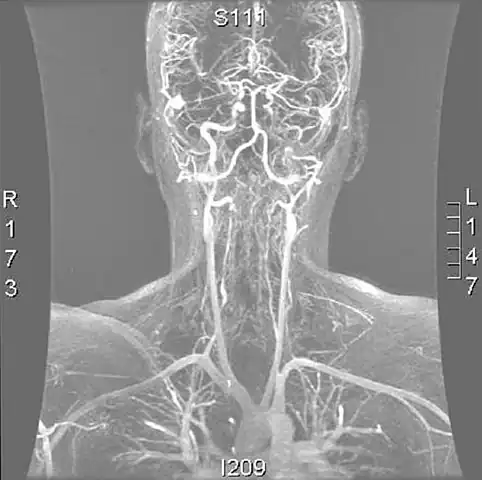

Cerebral vessels by brain MRA show cerebral atherosclerosis (and minor angiostenosis)

Angio MRI of supra-aortic vessels after the injection of 20cc of gadolinium for contrast